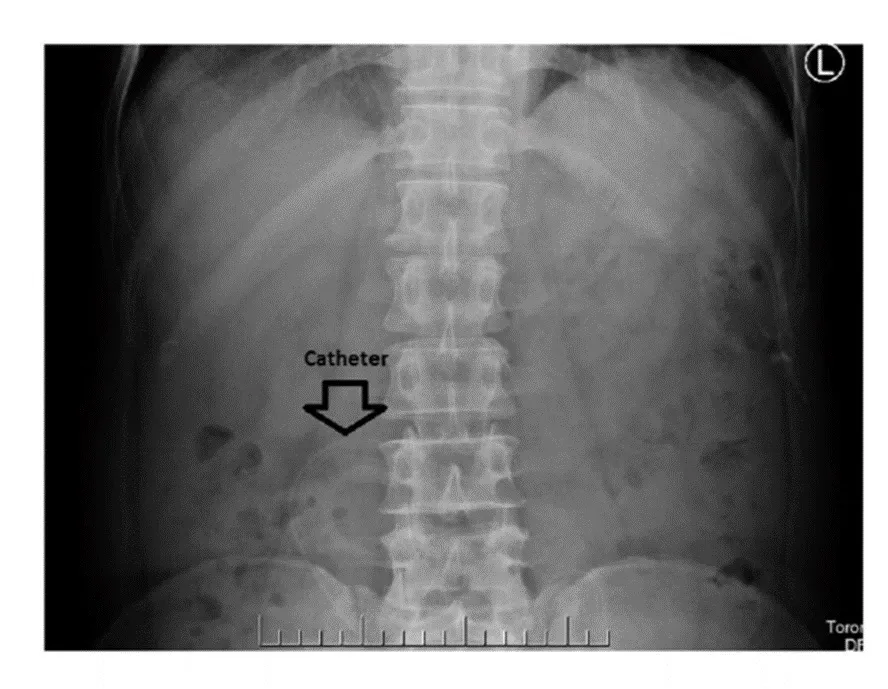

Complicações mecânicas relacionadas à diálise peritoneal (parte 3)